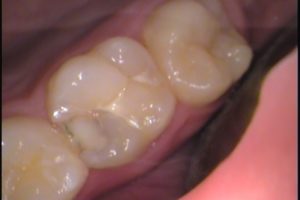

あとは、虫歯を丁寧に慎重に取り除き、

レジンで詰めて形を成形します。

虫歯がすべて痛みを感じるわけではありません。

痛みを感じた時は、神経にばい菌が入り、神経を取らなければいけない状態かもしれません。

早めの治療は、1回で済み、銀歯を入れなくてもすみます。

早期発見、早期治療を心掛けましょう(^^)/